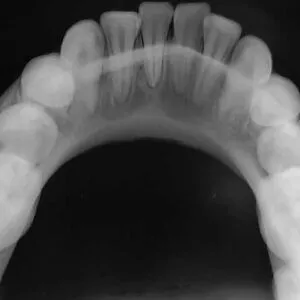

An occlusal x-ray is larger than a usual x-ray. This kind of x-ray highlights tooth development and placement of teeth in children and shows the full arch in either the upper or lower jaw.